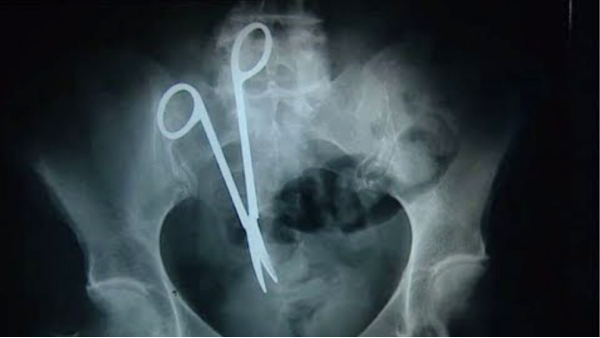

ऑपरेशन कर महिला के पेट से एक फोरसेप (सर्जरी में इस्तेमाल की जाने वाली मेटल की कैंची) निकाली गई है जो 10 साल पहले नसबंदी के दौरान डॉक्टर्स की लापरवाही के कारण पेट में ही रह गई थी।

बताया जाता है कि डॉक्टरों ने 10 साल पहले महिला की नसबंदी के ऑपरेशन के बाद कैंची पेट में छोड़ दी थी। महिला के परिवार ने 10 साल बाद महिला का एक्सरे निकलवाया तो उसकी रिपोर्ट देख हैरान रह गए। एक्सरे में महिला के पेट में एक अजीब चीज नजर आई।

जानकारी मुताबिक सीतामऊ नगर की रहने वाली महिला ने दिसंबर 2014 में जिले के ही शामगढ़ नगर के स्वास्थ्य केंद्र में अपने दो बच्चों के बाद नसबंदी का ऑपरेशन कराया था। महिला का ऑपरेशन करने वाले डॉक्टरों ने ऑपरेशन के दौरान लापरवाही बरती और महिला की जान के साथ खिलवाड़ किया। पति निलेश का आरोप है कि दस साल पहले हुए नसबंदी ऑपरेशन के दौरान डॉक्टर ने आर्टीपोरसेफ (कैंची नुमा टूल) महिला के पेट में ही छोड़ दिया था।

महिल ने 30 जुलाई 2024 को सीतामऊ के शासकीय अस्पताल पेट दर्द का इलाज कराने पहुंची। पति ने लंबे समय से इस परेशानी का होना बताया तो डॉक्टरों ने महिला के पेट का एक्सरे कराया। जब एक्सरे सामने आया तो चौंकाने वाली रिपोर्ट सामने आई है। महिला के पेट में कैंची नुमा आकार का जिसे मेडिकल भाषा में 'आर्टीपोरसेफ' कहा जाता है वह दिखाई दिया। यह देख महिला, उसका पति और डॉक्टर हैरान रह गए। सितामऊ के डॉक्टरों ने महिला को जिला अस्पताल मंदसौर के लिए रेफर किया। इसके बाद महिला को ऑपरेशन के लिए हायर सेंटर रेफर किया गया।